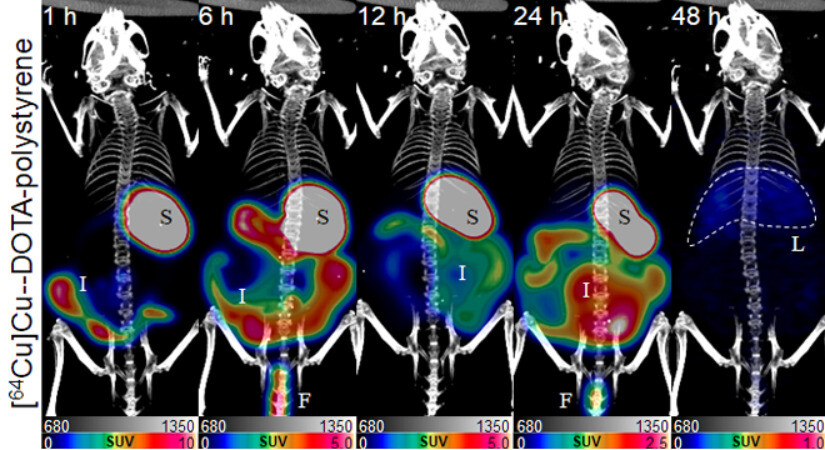

*연구팀은 실험용 쥐에게 먹인 방사성구리-폴리스티렌이 각종 장기에 머무는 경로를 시간대별로 관찰했다. 위와 장에서는 24시간 뒤 미세플라스틱이 대부분 빠져나가는 반면 간에는 1시간 뒤에 비해 48시간 뒤 5배로 증가했다.

연구팀은 0.2마이크로미터(㎛) 크기의 미세플라스틱 폴리스티렌에 방사성 동위원소 구리-64(Cu-64)를 붙인 60마이크로그램(㎍)의 방사성구리-폴리스티렌을 실험용 쥐에게 먹이고 펫 영상으로 이틀 동안 촬영했다. 1㎛는 100만분의 1m로, 머리카락 굵기가 80㎛ 정도 된다. 폴리스티렌은 일회용품이나 가전제품에 많이 쓰이는 열가소성 플라스틱의 일종이다.

연구팀은 펫 영상을 통해 미세플라스틱 이동 경로를 확인하기 위해 방사성구리-폴리스티렌 섭취 정도를 나타내는 ‘펫 표준섭취계수’를 분석했다. 그 결과 위와 장에서는 미세플라스틱이 24시간 정도 머문 뒤 대부분 몸 밖으로 빠져나간 것으로 나타났다. 반면 이틀이 지나 관찰한 간에서는 경구 투입 1시간 뒤보다 미세플라스틱 표준섭취계수가 5배 높아졌다.

연구팀은 펫 영상으로 관찰하기 어려운 부위의 미세플라스틱 분포를 확인하기 위해 실험용 쥐의 신체기관을 적출해 쥐가 먹은 방사성구리-폴리스티렌에서 방출되는 감마선을 측정했다. 이 분석에서도 미세플라스틱은 1시간 만에 각 기관에 퍼져나간다는 사실이 확인됐다. 또 생식기에서는 1시간 뒤에 비해 48시간 뒤 미세플라스틱이 3배 쌓이는 반면 뇌에서는 절반으로 줄어드는 것을 발견했다.

심장, 신장, 방광에서는 이틀 뒤 미세플라스틱 양이 처음에 비해 다소 늘어난 데 비해 폐와 비장, 혈액 등에서는 줄어들었다.